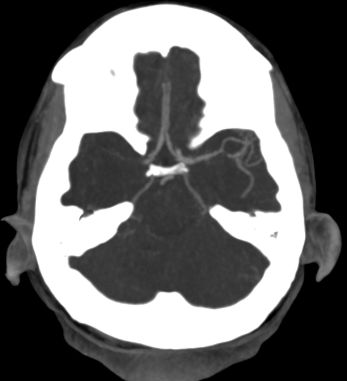

4/ 🐱 #CT head done with #ASPECTS 10, but #CTA reveals this:

Posts Media Videos Starter Packs

10/ Despite anticoagulation, pt presents several months later with left sided weakness, neglect, gaze deviation again 😩! #CT 🐱scan again with no acute stroke, evidence of prior stroke, but CTA again with right M1 occlusion!!!

emcrit.org/ibcc/dka/#top #EMIMCC

5/ Patient receives TNK and undergoes thrombectomy with great outcome! (pre/post angio, MRI DWI)

Reposted by Richard Choi, DO, FNCS